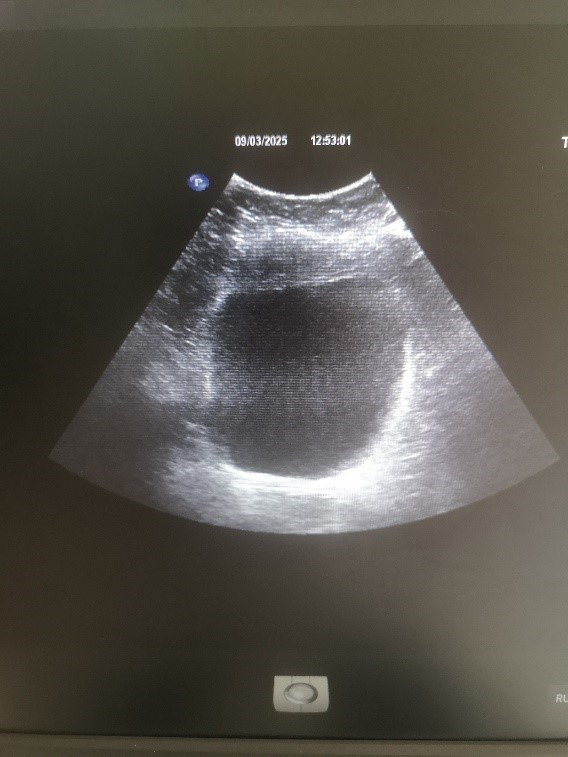

УЗИ надпочечников (рисунок 6). Левый надпочечник: размеры 24×20 мм, форма обычная, контуры четкие, ровные, структура однородная, эхогенность нормальная, положение типичное. Правый надпочечник: размеры 26×22 мм, форма обычная, контуры четкие, ровные, структура однородная, лоцируется гипоэхогенное образование размерами 17×13 мм с периферическим кровотоком при цветном доплеровском картировании, эхогенность нормальная, положение типичное.

Рис. 6. УЗИ правого надпочечника. В структуре обнаружена аденома

Fig. 6. Ultrasound of the right adrenal gland. An adenoma was found in the structure

Заключение. Выявлено в структуре правого надпочечника гипоэхогенное образование размерами 17×13 мм с периферическим кровотоком.